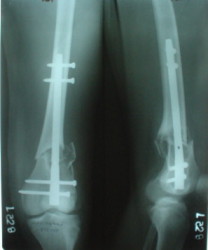

Мужчина 52 лет оперирован у нас 1,5 года назад по поводу перелома проксимального отдела большеберцовой кости. Все было неплохо, сгибал колено градусов до 60, ходил с полной нагрузкой, давно уже работал (служащий). Пару дней назад упал на скользкой улице - снимок в приложении. Какие предложения по лечению (пока первая мысль опять про закрытый интрамедуллярный остеосинтез)? И более широкий вопрос - как быть с локальным остеопорозом от бездействия после травм?

Merry Xmas!!! A male 52 years old was treated 1,5 years ago in our unit - ORIF of the proximal tibia. In 1 year follow-up all was OK - flexion 130, full WB, returned to work (white collar). Two days ago he fell on a slippery sidewalk - x-rays attached. How would you manage the injury? My first thought is closed nailing. And more common question - what we should do routinely with posttraumatic local osteoporosis? When full WB and function of the extremity is restored how long does a problem of such fractures exist?